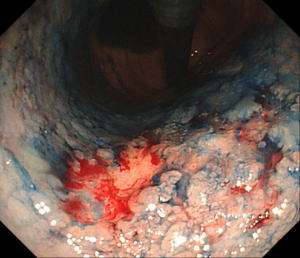

| 【胃ESD】 |

胃体部(胃の中部)小弯に発見されたやや広範囲の早期胃癌。癌の範囲をわかりやすくするため、インジゴカルミンという青い色素を散布しています。 |